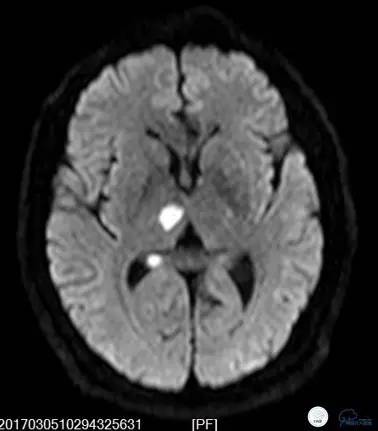

就诊于外院查头颅核磁DWI+MRA(图1-2):中脑右侧及右侧丘脑新鲜脑梗死,椎基底动脉及双侧大脑后动脉未见显影。住院予波立维、拜阿司匹林抗血小板聚集、立普妥降脂治疗后症状无好转,病情逐渐加重。为进一步行血管内治疗来我院。

图2